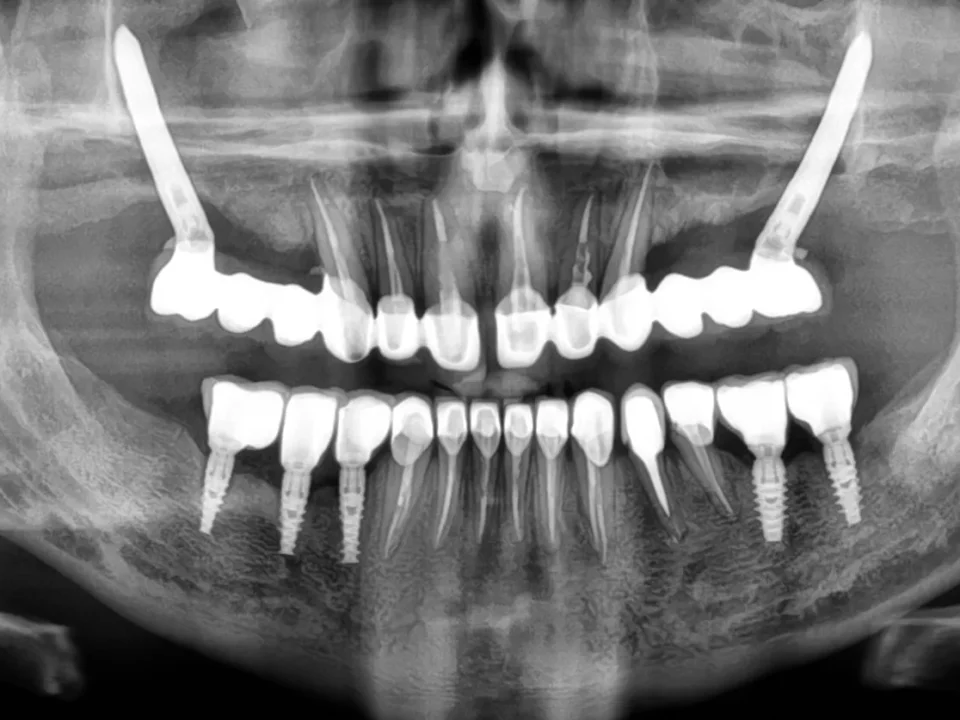

Implanty zygomatyczne – czym są? Z czego zostały wykonane i jakie są wskazania, by zastosować je u pacjenta? Rodzaje implantów zębowych Na jakie rodzaje dzielą się implanty zębowe? Klasyfikacje i kryteria podziału są różne. Pierwszy podział uwzględnia czas, na jaki […]